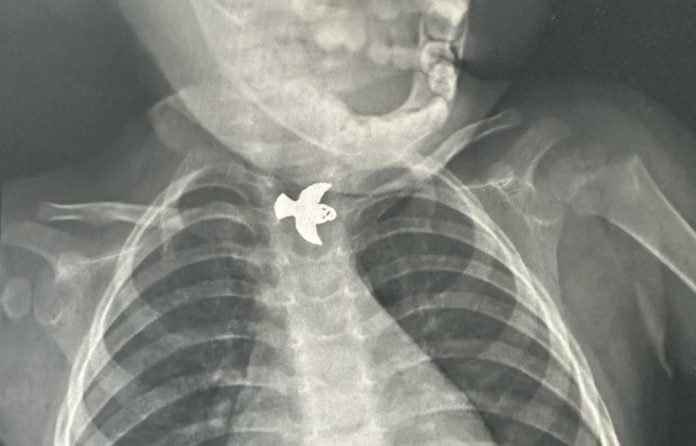

O HMSA também é referência no município do Rio de Janeiro para retirada de corpos estranhos. Em julho de 2024, a unidade realizou 236 atendimentos com esta finalidade. São desde objetos engolidos a inseridos no ouvido ou nariz, especialmente por crianças.

“No hospital, contamos com um serviço de urgência e emergência com décadas de experiência em retirada de corpos estranhos, que gerou, inclusive, um grande museu com a diversidade dos objetos que já foram extraídos. Mas a principal mensagem que precisamos deixar é a necessidade de supervisão reforçada dos pequenos durante esse período. Estar atento à classificação indicativa de brinquedos e à acessibilidade de pequenos objetos é primordial para evitar acidentes. As crianças são naturalmente curiosas e podem facilmente conduzir esses materiais à boca, nariz ou ouvidos”, ressalta Edio Cavallaro, chefe do serviço de Otorrinolaringologia do HMSA.